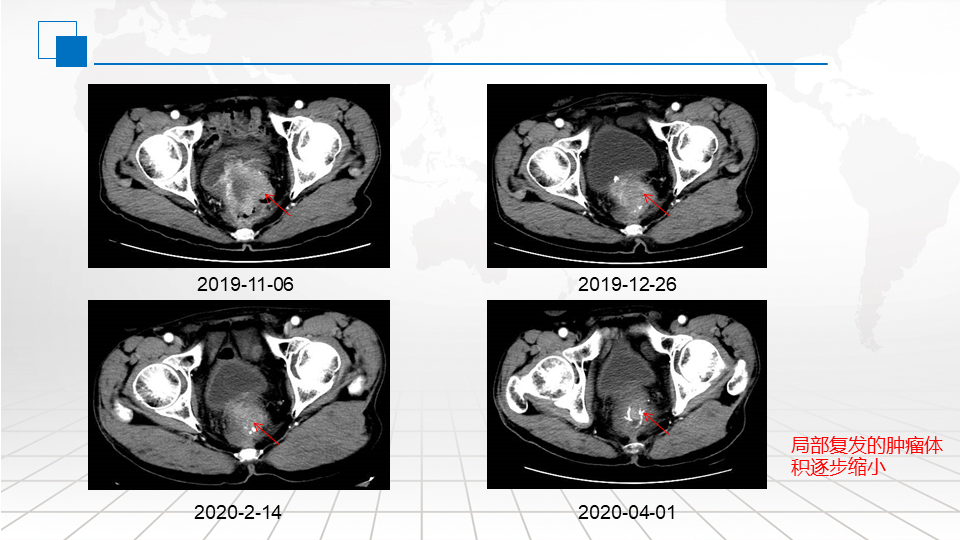

行腹盆腔CT检查提示:直肠癌术后,吻合口周围软组织密度影,考虑复发,累积膀胱后壁。肝左叶术后改变,残肝实质密度未见明显异常。

患者肛门坠胀伴疼痛,伴有小便带血,局部症状较重,需要快速缩瘤、缓解症状。结合患者既往基因检测结果,后患者分别于2019.11.24、2019.12.10、2019.12.27、2020.1.15、2020.1.31、2020.2.15、2020.3.2、2020.3.17在我科行西妥昔单抗700mg +伊立替康240mg d1 +卡培他滨1.5g bid d1-7,治疗8周期,每2周重复。患者治疗期间一般情况尚可,未见明显不良反应。

治疗期间,患者肛门坠胀感、疼痛感,小便带血症状明显改善。复查肿瘤标志物CEA持续下降;局部复发肿瘤体积逐步缩小。2020.04.01复查CT评估病情PR。肿瘤标志物CEA已降至正常。